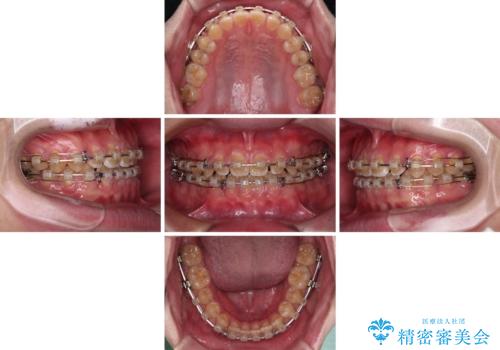

- クリアブラケット

- 3年2ヶ月

- 10-30回

舌の突出癖がなかなか改善されず、治療期間は当初予定よりも大分長くなりました。

装置除去を予定していた日に、油断されたのか1mmほどのスペースを作ってしまったため、除去が3ヶ月延長されたことで、舌のトレーニングの重要性を理解していただきました。